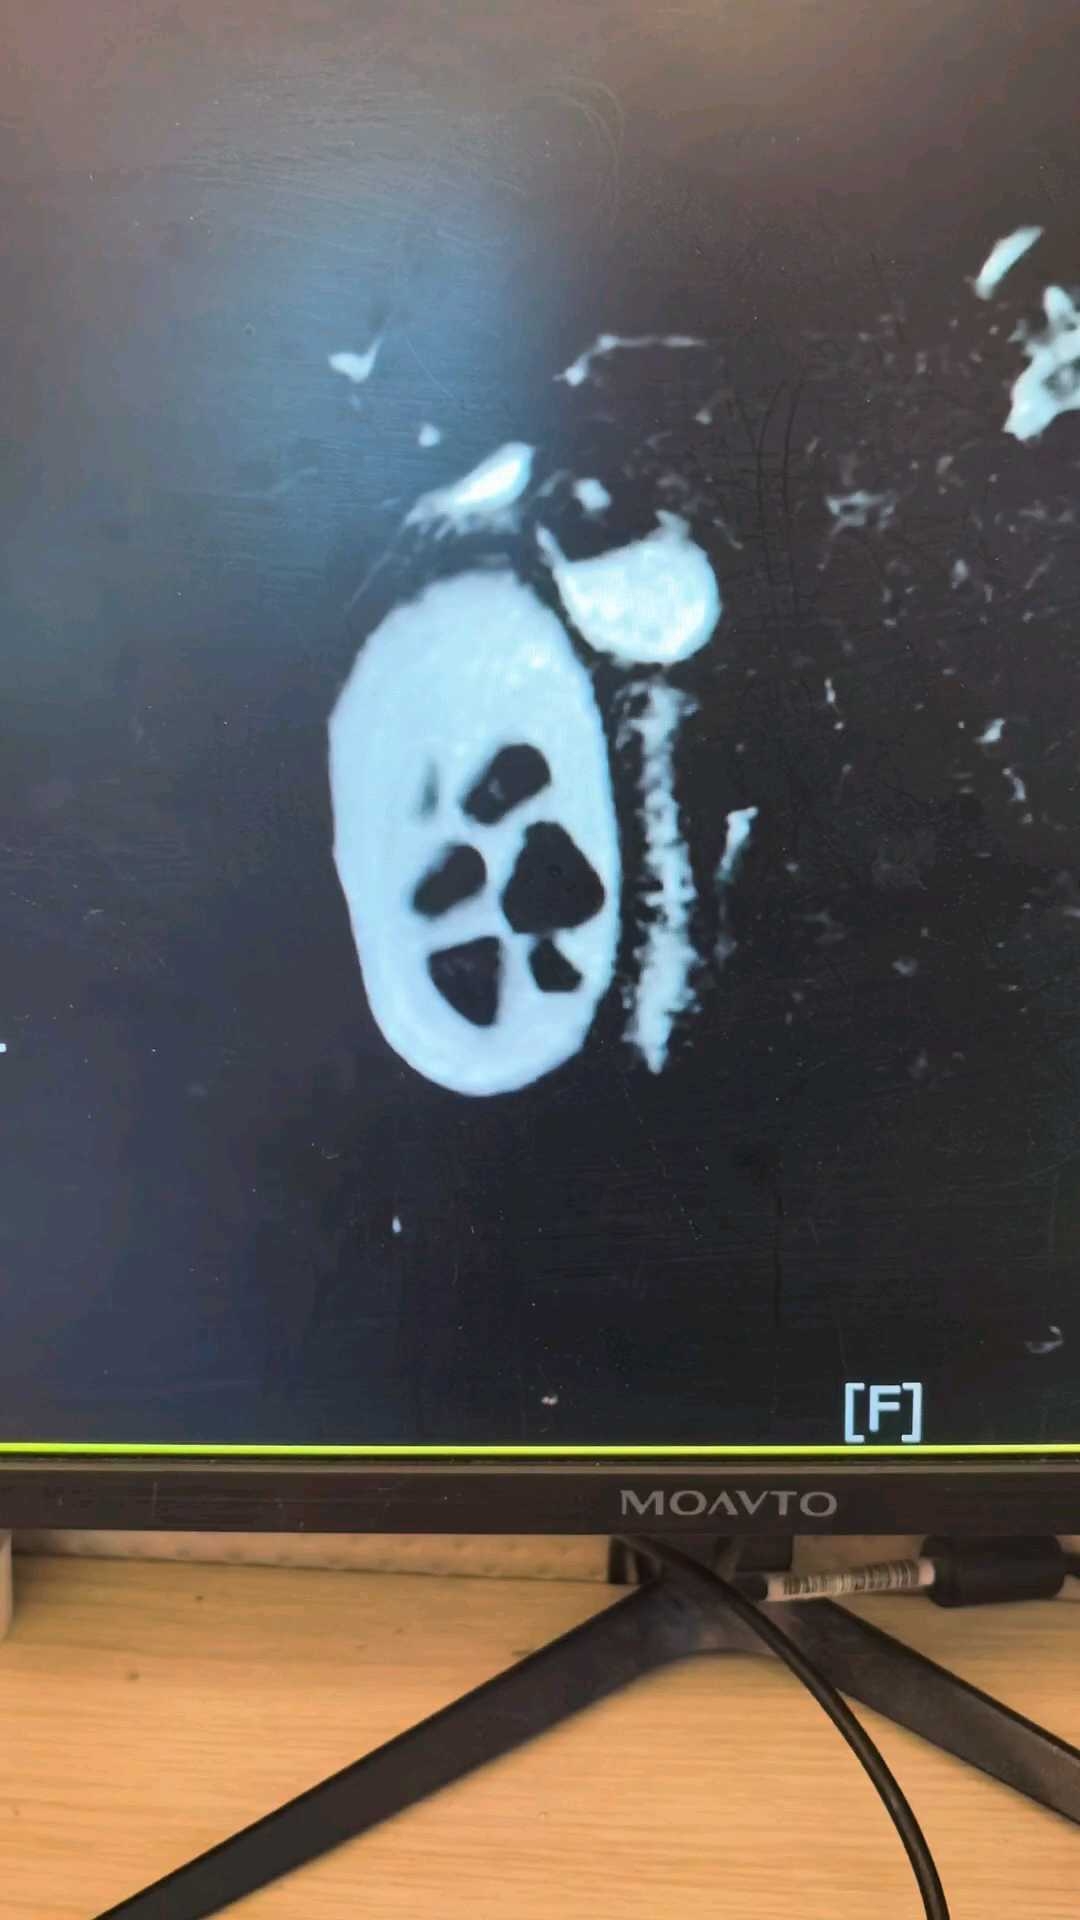

一台特殊的LC术前MRCP:

img

好在安全拿下LC,您看?

胆道先天性畸形 (1)